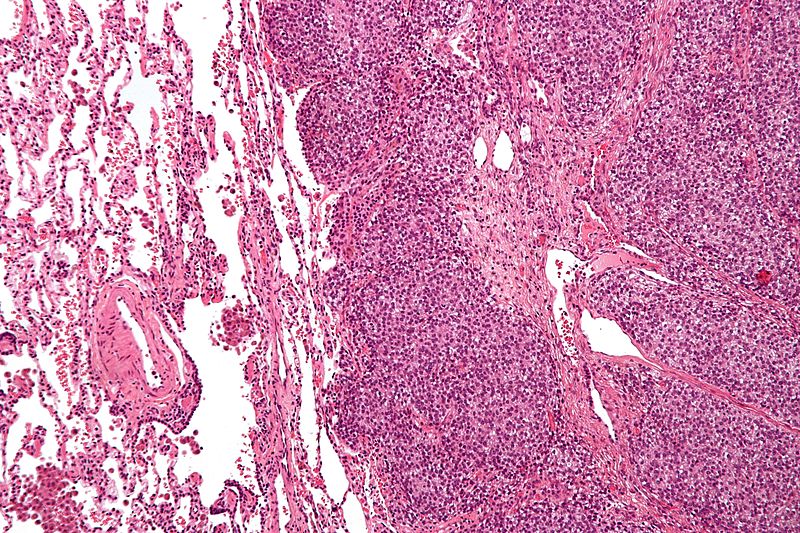

Ewing Sarcoma

Ewing sarcoma is characterized by the malignant proliferation of poorly differentiated cells.

Diagnosis of Ewing sarcoma is made by biopsy that reveals small, round, blue cells that look similar to lymphocytes.

Malignant cells of Ewing sarcoma stain positive for CD99.